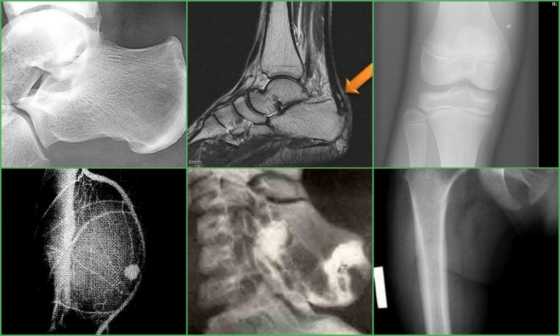

В нашей клинике стандартным методом диагностики является рентгенологическое исследования. На рентгенограммах остеохондромы определяются как локальное выбухание кости. Все экзостозы исходят из кости на узкой или на широкой ножке. От этого зависит эволюция остеохондром и выбор тактики лечения.

Основным методом диагностики является рентген в 2-х проекциях. На снимках визуализируется только костная часть опухоли в виде новообразования с четкими границами и соединенного тонкой ножкой или толстым основанием с материнской костью. Также наблюдается истончение кортикального слоя кости, а сама остеохондрома часто имеет вид «цветной капусты» из-за участков обызвествлений в хрящевой шапочке.

Сам хрящевой колпачок на рентгеновских снимках не отображается, хотя его величина важна для определения вероятности озлокачествления. В норме толщина хрящевого слоя не должна превышать 1,5—2 см. Поэтому в спорных случаях, а также детям с высокой скоростью роста остеохондромы нередко дополнительно назначается проведение КТ или МРТ. В результате удается не только точно визуализировать хрящевую шапочку, измерить ее параметры, но и определить расположение сосудисто-нервного пучка, а также оценить состояние плечевого, локтевого сустава или кисти. Это дает возможность разработать оптимальную тактику лечения.